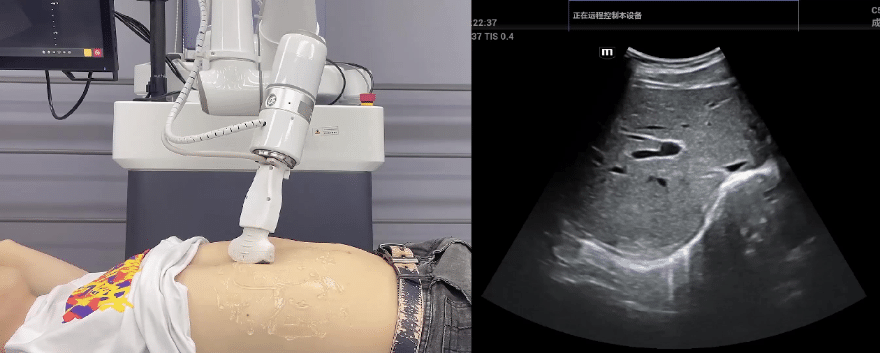

艾利特協(xié)作機(jī)器人搭載庫(kù)柏特自主研發(fā)的機(jī)器人遙操作、多模態(tài)數(shù)據(jù)采集與處理、機(jī)器人模仿學(xué)習(xí)、機(jī)器人力位控制等技術(shù)升級(jí)變革傳統(tǒng)超聲,可實(shí)現(xiàn)遠(yuǎn)程+自主超聲掃查與診斷,從傳統(tǒng)遠(yuǎn)程超聲僅能對(duì)話會(huì)診變革升級(jí)為能對(duì)話、能操作,使得基層患者可就近享受異地三甲專家掃診服務(wù)。實(shí)現(xiàn)專家端與患者端遠(yuǎn)程連接,并支持專家端與多路患者端自由切換控制。

艾利特協(xié)作機(jī)器人與超聲深度打通,最大程度保留醫(yī)生左右手同時(shí)操作傳統(tǒng)超聲的習(xí)慣,并改善其舒適性,超聲檢查實(shí)際應(yīng)用場(chǎng)景展示如下:

肝臟、膽囊、胰腺掃查